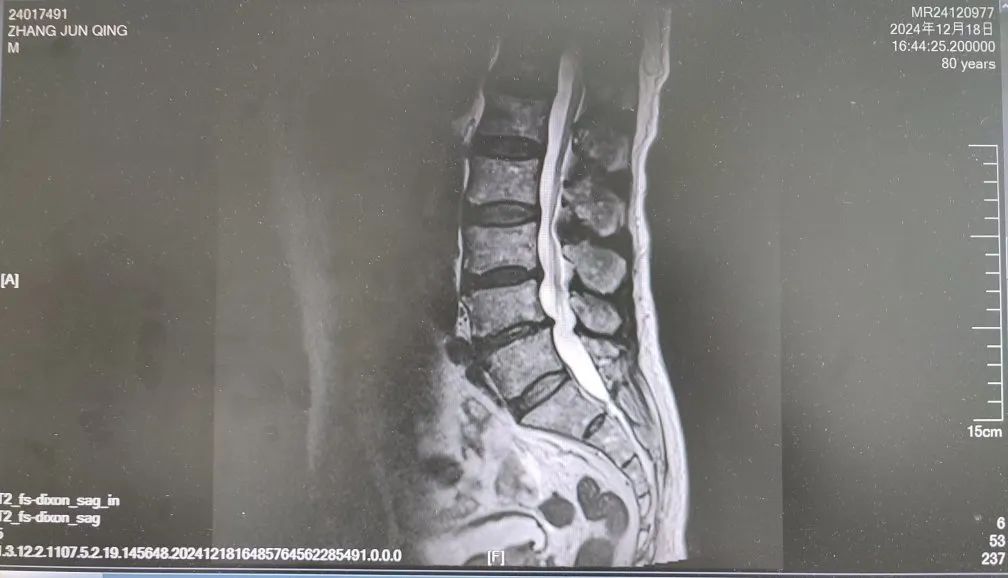

内容提要 很多人都想拥有纤细、健美的双腿,尝试多种健身方法,效果却始终不理想。然而社会上大约有万分之四的人,他们不用减肥,双腿就会慢慢“瘦”下来,如倒置的香槟酒瓶,医学中称之为“鹤腿”。不过这并非自愿,而是源于一种名为“腓骨肌萎缩症”的罕见疾病。近日,市二院神经内二科赵智江主任团队就帮助一位受腓骨肌萎缩症困扰4年之久的患者明确了病因。 #01 “鹤腿”多年不明病因 竟是罕见病作祟 患者80岁,四年前无明显诱因出现步态异常,行走困难,起初以为是劳累所致,并未过多在意。然而,近一年来症状逐渐加重,双下肢膝关节以下麻木、发凉,行走时右下肢有甩脚动作,呈跨阈步态,右足趾背屈不能,同时存在站立不稳、不能蹲下等症状,严重影响日常行走。这一年间,他辗转市内多家医院,经历了无数次的检查和咨询,却始终未能得到确切诊断。 近日,患者经多方打听,来到了以诊治神经疑难病为特色的市二院神经内二科。入院后,赵智江主任为患者进行了细致入微的查体,发现患者双侧大腿下三分之一处及小腿肌肉萎缩。进一步完善头颅、颈椎及胸椎核磁的检查,由于患者存在跨阈步态,结合检查结果,初步考虑为腓总神经麻痹。 头颅、颈椎核磁回报后,基本上排除了神经根的疾病和脊髓疾病。肌电图结果提示四肢周围神经受累,右侧腓总神经损伤更重,修正诊断为周围神经病。然而,周围神经病存在多种病因,需进一步查找病因。赵智江主任结合患者双下肢肌肉萎缩情况,排除其它病因导致的周围神经病,最终明确诊断为腓骨肌萎缩症。 头颅核磁影像 颈椎及腰椎核磁影像 随后,中国医科大学附属第一医院神经内科著名专家何志义教授及辽宁名医、市二院卒中中心主任闵连秋教授在查房时同样肯定了腓骨肌萎缩症的诊断。 腓骨肌萎缩症是一组具有高度临床和遗传异质性的周围神经单基因遗传病,以慢性进行性四肢远端肌无力肌萎缩、末梢型感觉障碍、腱反射减退或消失和高弓足等骨骼畸形为主要临床特征,多为儿童和青少年期起病。该患者老年起病,极为罕见!目前,腓骨肌萎缩症无特效治疗药物,主要以支持治疗为主。今后,患者只要在康复医师的指导下,根据神经损害范围进行合理的康复锻炼,就能保持较好的活动能力,提高生活质量。 市二院神经内二科赵智江主任团队拥有丰富的神经系统疑难疾病诊治能力,曾帮助大量饱受罕见病困扰多年的患者明确了诊断。随着诊疗水平的持续精进,神经内二科将为更多患者提供精确诊断及治疗,为更多的神经疑难疾病明确诊断,为患者带来福音。 #02 人民医院 人民名医 赵智江 主任医师 副教授 ·葫芦岛市第二人民医院神经内二科主任 ·中国卒中学会高级会员 ·中国老年保健医学研究会老年脑血管病分会委员 ·北京神经内科学会脑小血管病学会委员 ·安徽医药杂志审稿专家 专业特色:以脑血管病为核心研究方向,擅长各类神经系统疾病的诊疗,尤其在脑血管病、帕金森综合征、头晕、头痛、癫痫、重症肌无力以及中枢神经系统脱髓鞘等神经系统疑难、危重疾病的诊疗方面积累了丰富的临床经验。主持多项重要科研项目,并将最新的科研成果应用于临床实践,撰写十余篇论文著作。